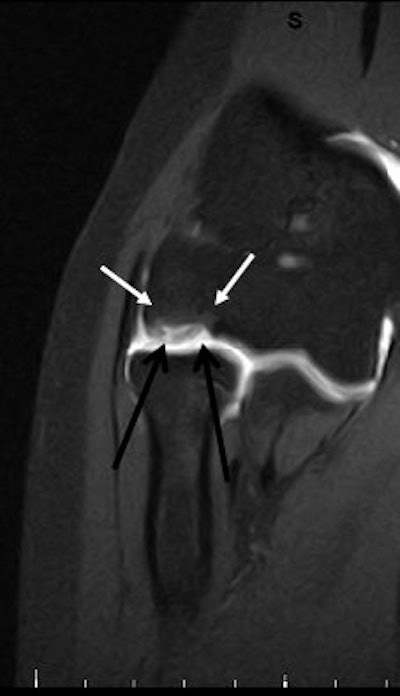

|  |

| Above and below, OCD of the medial femoral condyle in a female child. Images courtesy of Dr. Douglas Beall. |